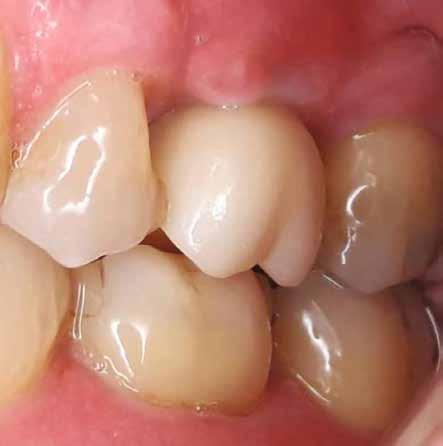

8. a–b. ábra: Végső röntgenfelvétel az implantátum helyzetéről (a) és a szájon belüli végső szituáció az 1. esetről (b).

9. a–b. ábra: Végső röntgenfelvétel az implantátum helyzetéről (a) és a szájon belüli végső szituáció a 2. esetről (b).

10. a–c. ábra: Végső röntgenfelvétel az implantátum helyzetéről (a) és a szájon belüli végső szituáció a 3. esetről (b és c).

tottuk (az okklúziós koncepciók alapján az implantációs pótlások nem voltak vezető fogak, és csak könnyű érintkezéseket alakítottunk ki, amelyeket artikulációs papírral ellenőriztünk). A páciensek instrukciókat kaptak a megfelelő szájhigiénére vonatkozóan, összpontosítva a fogköz kefékkel történő tisztítására. Végső kontroll röntgenfelvétel készült. A PEEK felépítmény nem radioopák, így az implantátum és a korona közötti távolság könnyen meghatározható a röntgenfelvételen: a felépítmény megfelelően illeszkedik az implantátumban, ha az implantátum válla és a korona alsó széle közötti rés 0,55 mm a röntgenfelvételen (8–11. ábra)

11. a–b. ábra: Végső röntgenfelvétel az implantátum helyzetéről (a) és a szájon belüli végső szituáció a 4. esetről (b).